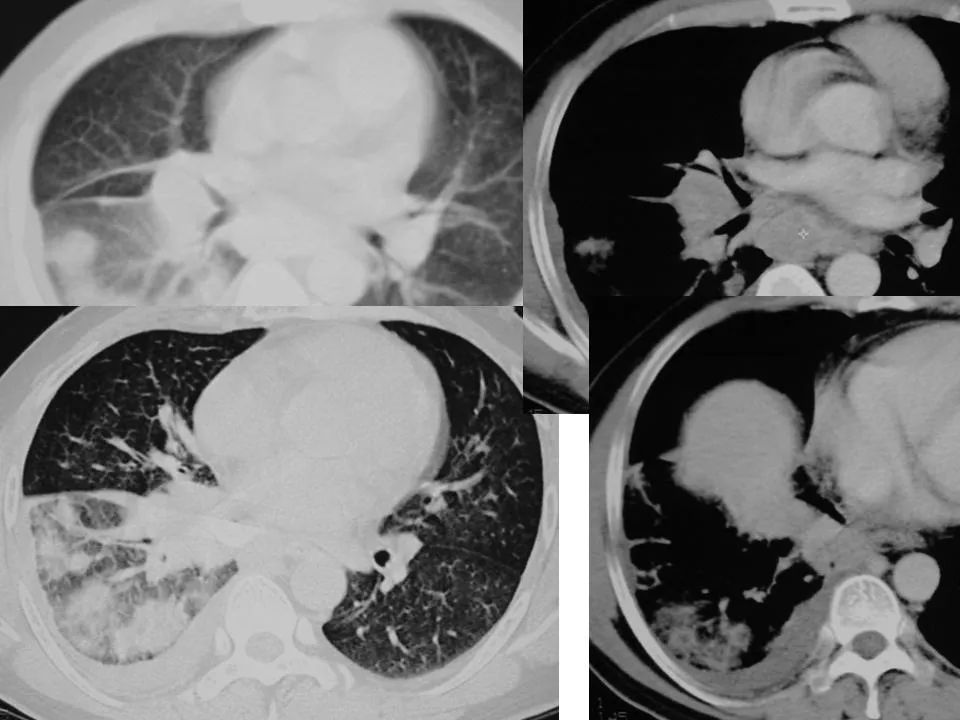

弥漫型细支气管肺泡癌化疗有效1例并文献复习

弥漫性细支气管肺泡癌(bac)